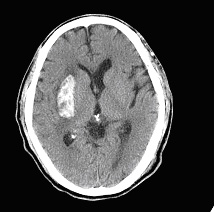

右側大腦出血性腦中風